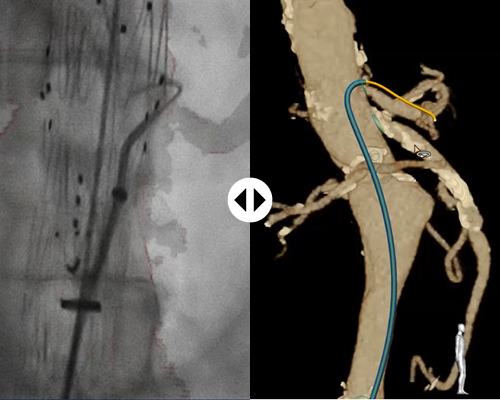

Unprecedented viewing clarity

Visualize your catheter of choice

Thanks to 3D Hub technology, you can continue to work with the catheters you’re already used to. The 3D Hub, in combination with FORS-enabled guidewires, enables your catheters to be visualized inside the body.

- Is X-ray still necessary when conducting a FORS-enabled procedure?

-

X-ray is still necessary to visualize the patient anatomy. FORS technology only visualizes devices. However, FORS has already been shown to reduce radiation exposure, for the patient and staff, during complex aortic procedures.

- Can I continue to use the catheters I’m familiar with?

-

Yes. FORS has been specifically designed to work with standard catheters, in combination with the Philips 3D Hub. The Fiber Optic RealShape technology is integrated into the guidewire that the catheter slides over, and not the catheter itself.